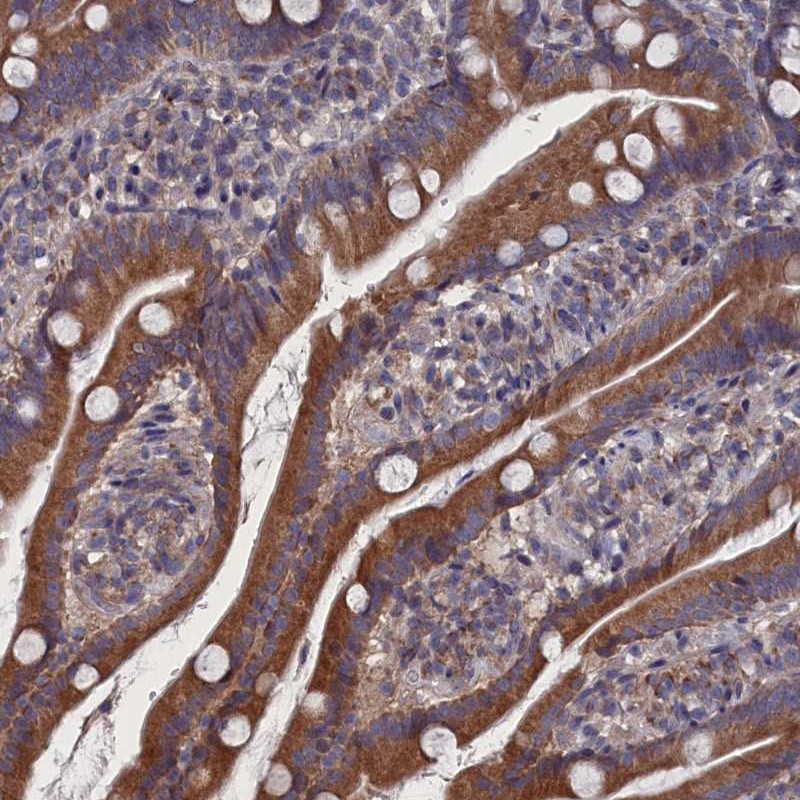

Immunohistochemical staining of human duodenum shows distinct cytoplasmic positivity in glandular cells.